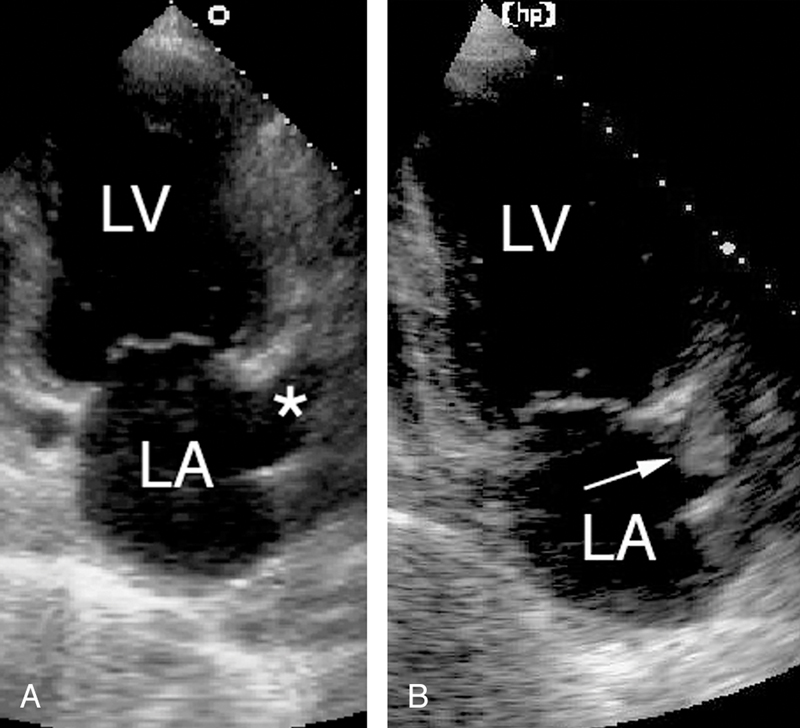

فحوصات تشخيصية لبعض امراض القلب والشرايين التاجية